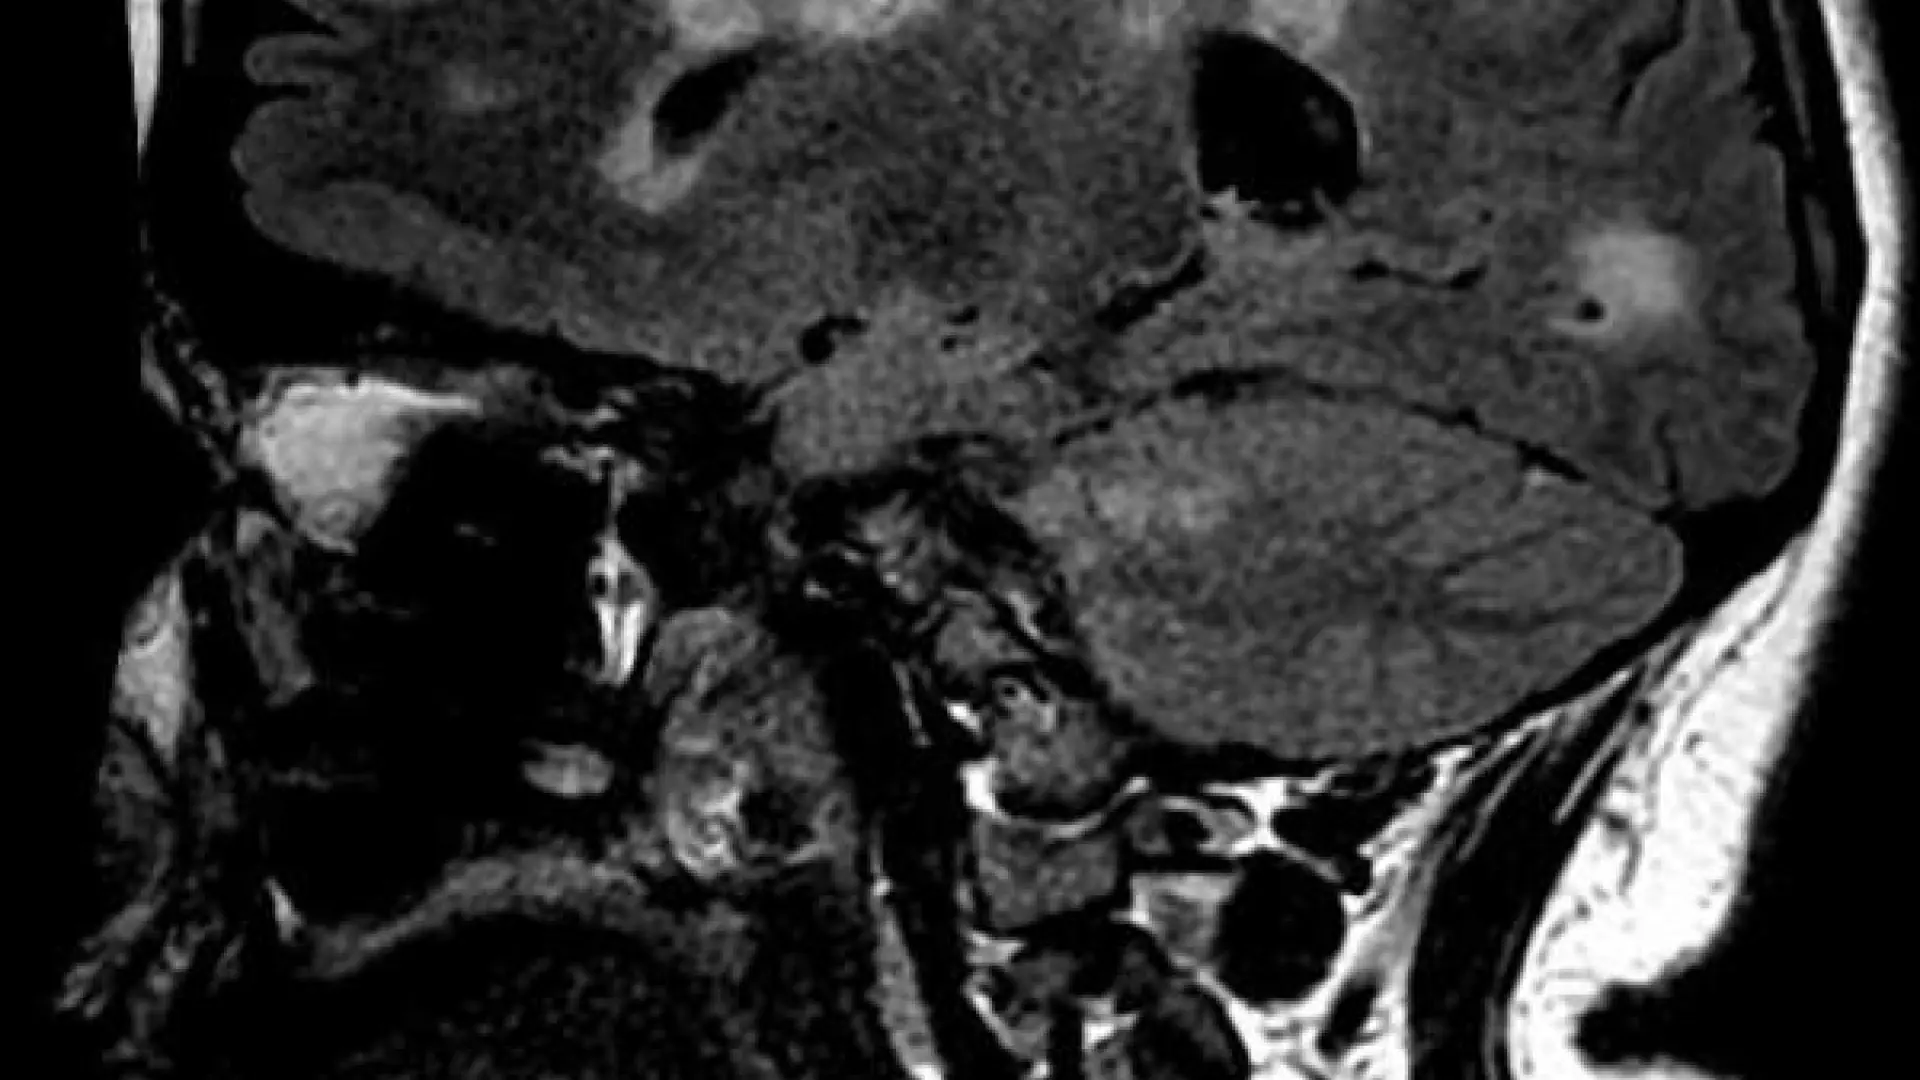

Otro estudio apunta a la relación entre el virus de la mononucleosis y la esclerosis múltiple

Redacción Ciencia, 13 ene (EFE).- El virus común de Epstein-Barr, que provoca la mononucleosis, causa una reacción del sistema inmunitario que puede dañar el cerebro y contribuir a la esclerosis m...